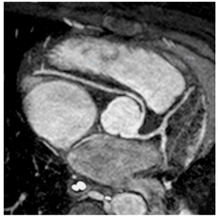

Heart Muscle Problems (Cardiomyopathies and Myocarditis)

Description: There are many types of heart muscle problems that can affect children. Cardiomyopathies are due to genetic, or inherited, conditions that can cause the heart chambers to become enlarged, the heart muscle to thicken, or other changes with the muscle. Myocarditis can cause damage to the heart muscle after an infection.

Why MRI: Heart MRI is used to capture pictures of the heart chambers and muscle to help figure out the type of heart muscle problem that a child has or if there are changes over time. It is also used to measure how well the heart is pumping. Sometimes Heart MRI will be used to look for any scar or damaged areas.

Images: DCM, HCM, LGE, T1/T2 map